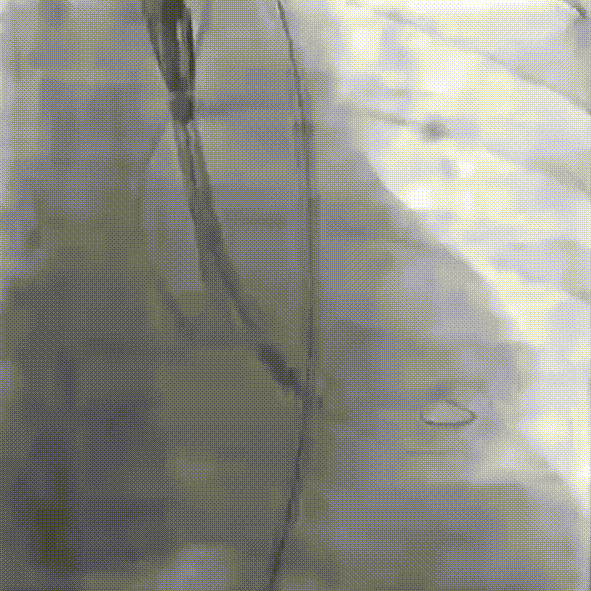

稳定脱钩

最终造影,位置形态良好